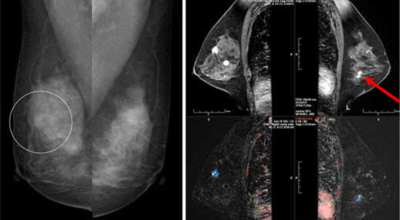

유방 밖으로 퍼진 악성 종양으로 생명을 위협할 수 있어요. 유방암은 보통 유방의 유관과 소엽에서 생기는데요 남성도 드물게 유방암에 걸릴 수 있어요. 유방암은 아직 명확한 원인이 알려지지 않았어요. 하지만 여러 가지 위험 요인을 추정할 수 있는데요 유전, 호르몬, 노화, 음주, 비만 등이 있답니다. 가장 흔한 증상은 유방에 발생하는 종괴입니다. 그리고 유두 분비, 유방통, 피부궤양, 함몰, 겨드랑이 종괴 등이 나타날 수 있어요. 증상들이 꼭 유방암을 나타내는 것은 아닐 수도 있으므로 정확한 검사가 필요하다고 해요.